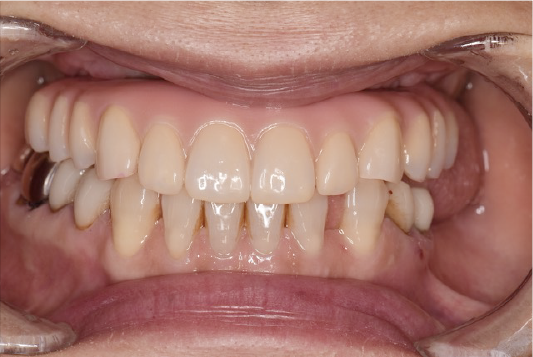

CASE02

■ 治療内容

上顎オールオン4インプラント治療(4本頬骨インプラント)

■ 治療費用

(モニター)3,330,000円(税込)

■ 治療期間

約10ヶ月

■ リスク

治療後の腫れや出血、またメンテナンスを怠ることで周囲炎のリスクあります。